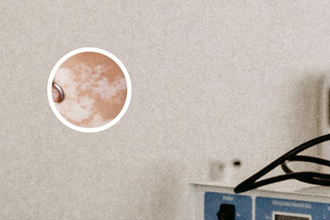

白癜風病變的初期往往表現(xiàn)為局部的輕微色素喪失,可能表現(xiàn)為白色、粉色或稍微淡色的斑塊。手部是一個容易受到外界刺激的部位,日常生活中經常接觸各種物體和化學物質,這些刺激可能會導致皮膚色素的喪失,從而出現(xiàn)白癜風的初期病變。

白癜風初期確實有可能出現(xiàn)在手上。醫(yī)學表現(xiàn)可以是局部的輕微色素喪失,并可能伴有輕微瘙癢、干燥和脫屑等癥狀。然而,這并不意味著手部病變就一些是白癜風的初期表現(xiàn),因為白癜風的確診還需要進一步的檢查和評估。

我們需要明確一點,白癜風是一種與色素細胞功能障礙相關的疾病,它會導致皮膚某些區(qū)域出現(xiàn)白斑。而白癜風初期的白斑往往會出現(xiàn)在面部、四肢等身體部位,包括手部。

白癜風初期在手上的表現(xiàn)形式可能因人而異。有些患者可能會出現(xiàn)手部的小面積白斑,而有些人可能會出現(xiàn)廣泛的白斑覆蓋手部。這取決于個體的病情和病變程度。一般來說,手部白斑更容易引起患者的關注和不適感。

盡管白癜風初期可能在手部出現(xiàn),但并不意味著所有手部的白斑都是白癜風。因為有些其他疾病或因素也可能導致手部出現(xiàn)類似的白斑,如真菌感染、過敏反應等。因此,如果您發(fā)現(xiàn)手部出現(xiàn)白斑,應及時就醫(yī),請專科醫(yī)生進行細致的診斷和鑒別。